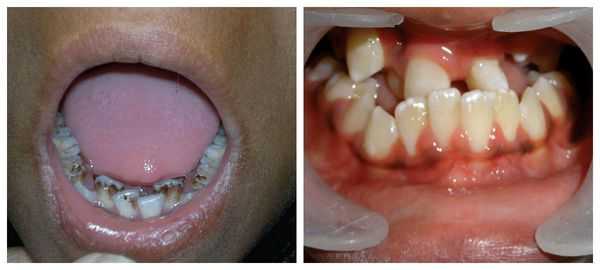

Нарушение развития зубного ряда проявляется пропуском некоторых зубов или наличием дополнительных, неправильным углом роста зубов, склонностью к кариесу. При таких нарушениях может потребоваться ортодонтическое лечение и коррекция прикуса, а иногда - пересадка лишних или имплантация недостающих зубов. У детей с заячьей губой отмечается нарушение процесса формирования звуков, что проявляется расстройством речевой функции (ринолалией). Речь у таких пациентов нечеткая, с выраженным носовым звуком («гнусавостью») и проблемным произношением согласных.

Большую опасность представляют нарушения потребления молока/смесей, из-за чего младенец недополучает нутриенты, отстает в физическом развитии, страдает от гиповитаминозов. По мере взросления беспокоят проблемы с прорезыванием зубов, аномалии прикуса, нарушения жевания. Вторичные функциональные осложнения появляются в раннем детстве и у дошкольников. Они включают снижение иммунитета, психоневротические проявления.